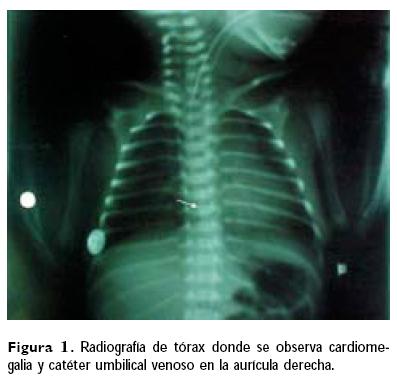

Caso 1. Se trató de producto de la primera gesta, embarazo normoevolutivo, que culmina en operación cesárea, obteniéndose recién nacido femenino de 35 semanas de edad gestacional por Capurro,6 con calificación de Apgar 8/9 en tiempos convencionales, Silverman/Andersen de 2, peso de 1 820 g. Se ingresó a la Unidad de Terapia Intensiva Neonatal (UTIN), donde se le colocaron catéteres umbilicales arterial y venoso, observándose en la radiografía de control datos compatibles con retención de líquido pulmonar y se observaron ambos catéteres colocados adecuadamente. Durante las primeras 24 horas de vida presentó tres períodos de apnea, por lo que se impregnó con aminofilina; presentando posteriormente apnea y bradicardia, se inició ventilación con presión positiva sin mejoría, llegando a la asistolia, manejándose con intubación endotraqueal, masaje cardiaco, adrenalina y bicarbonato de sodio, sin respuesta adecuada, se realizó radiografía de tórax, observándose cardiomegalia y el catéter umbilical venoso en la aurícula derecha (Fig. 1), por lo que se realizó punción pericárdica, obteniéndose 12 ce de líquido cristalino, al cual se le practicó una glucometría marcando elevado por exceder el límite máximo del equipo; presentó arritmia ventricular manejada con xilocaína, y posteriormente taquicardia supraventricular tratada con cardioversión eléctrica, revirtiendo a ritmo sinusal. Se extrajo el catéter venoso umbilical 2 cm y al día siguiente se retiró completamente y se colocó un catéter percutáneo en el miembro superior derecho. Ecocardiograma de control con derrame residual de 2 mm. Se realizó ultrasonido transfontanelar que resultó normal, evolucionando hacia la mejoría y se egresó sin secuelas a los 21 días de vida extrauterina.